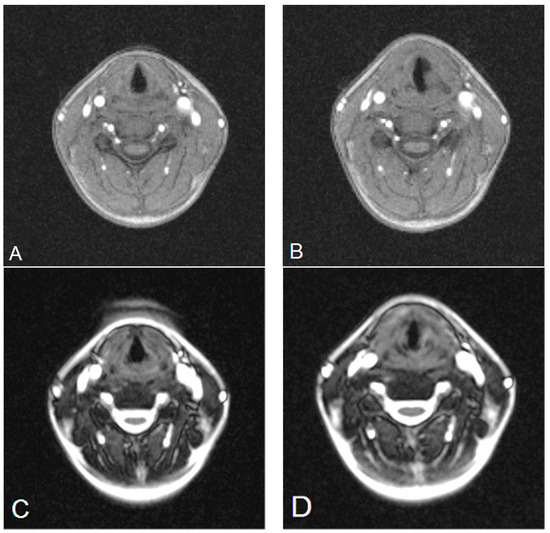

3.1. Analysis of the Qualitative Data Obtained during Ultrasound and MRI in Patients with Goiter Compared to Direct Laryngoscopy

3.2. Analysis of the Quantitative Data Obtained Using Ultrasound and MRI Methods (GRE and TRUFI Sequences) before and after Thyroidectomy

3.3. Analysis of the Quantitative Data Obtained with the Use of GRE and TRUFI Dynamic Sequences in the Group of Paralyzed Vocal Folds during Phonation